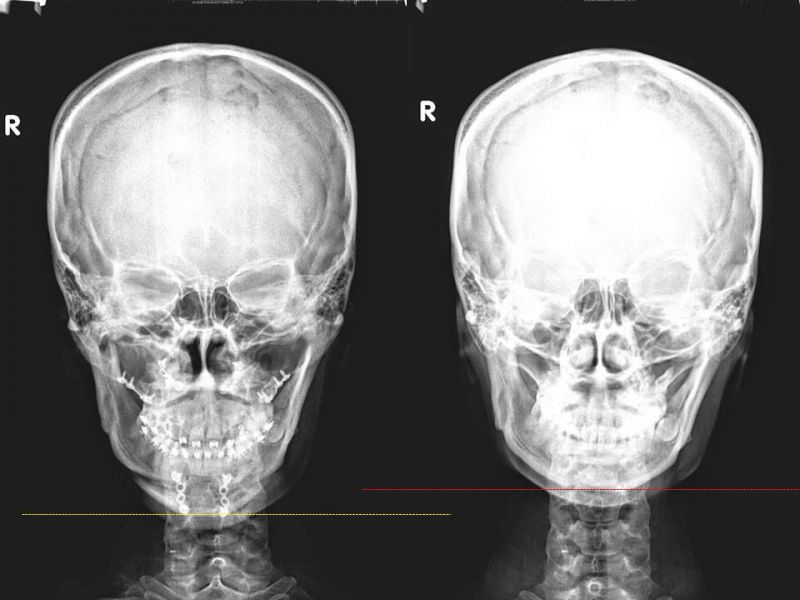

下图是一位上颚突出(暴牙)合并下颚后缩的案例(右侧手术前),一般的手术设计会将上颚往后移动同时将下颚往前拉,以便同时改善咬合及外观。但是因为单侧颞颚关节病变,我们采取了只做上颚及下巴的方式,仍然能够达到改善咬合以及外观的目的(左侧手术后)。

从正面可以看到手术后(左侧)下脸部的比例比起术前(右侧)明显增加,脸型也获得改善。